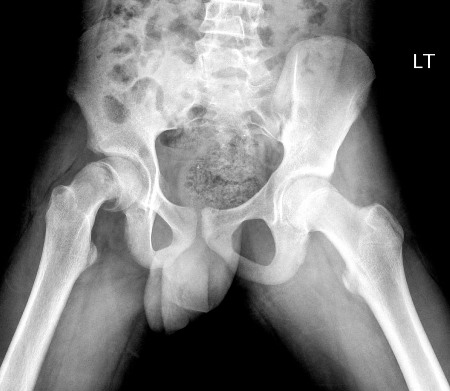

Radiografias simples devem ser solicitadas para todos os pacientes com suspeita de EPF. Na incidência anteroposterior, a linha de Klein, que é desenhada ao longo da região superior do colo do fêmur, normalmente faz intersecção com alguma parte da cabeça do fêmur em um quadril saudável.[Figure caption and citation for the preceding image starts]: Linhas de Klein são desenhadas ao longo do córtex superior do colo do fêmur. Uma linha de Klein normal fará intersecção com a epífise. Uma linha de Klein anormal não faz intersecção com a epífise, pois o colo do fêmur deslocou-se em direção proximal e anterior em relação à epífiseImagem cedida por John M. Flynn, MD [Citation ends].

Outros achados radiográficos podem incluir alargamento da fise no lado afetado, perda da sobreposição da metáfise do fêmur proximal (sinal de Capener) ou aumento da esclerose da metáfise proximal na visão AP, em que a epifisiólise se sobrepõe à metáfise como uma sombra dupla (sinal branco de Steel).[33][34]

A linha de Klein não faz intersecção com a cabeça do fêmur; pode mostrar alargamento da fise, perda do sinal de Capener ou sinal branco de Steel positivo